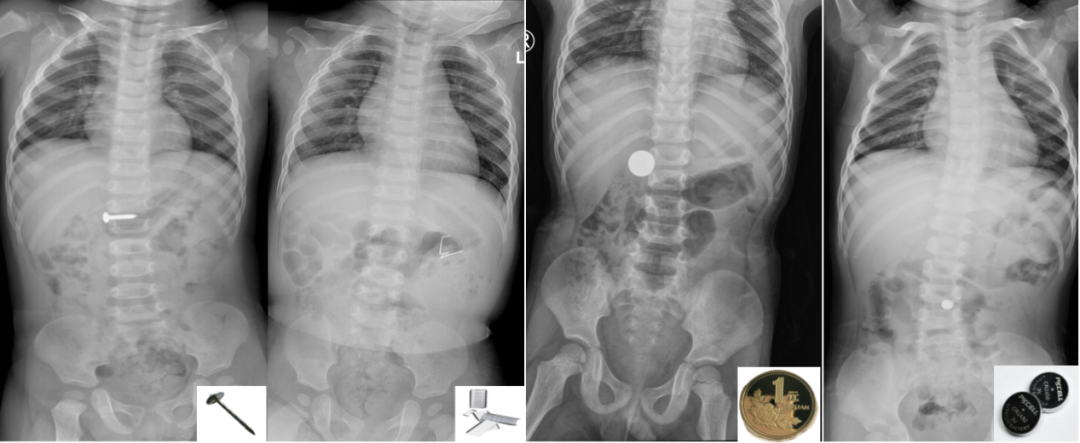

X线下的异物(从左到右:钉子、订书针、硬币、纽扣电池)